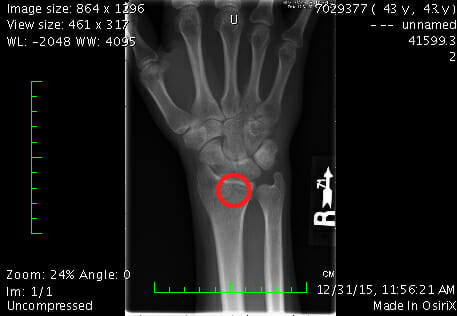

I know what you're thinking, and no... it wasn't the result of too much boozing. That would at least be a fun story to tell, but the truth is far more dull: I was spreading salt on our icy back steps when I slipped and fell. The resulting fracture was to my right-distal radius, where it articulates with the carpal (wrist) bones.